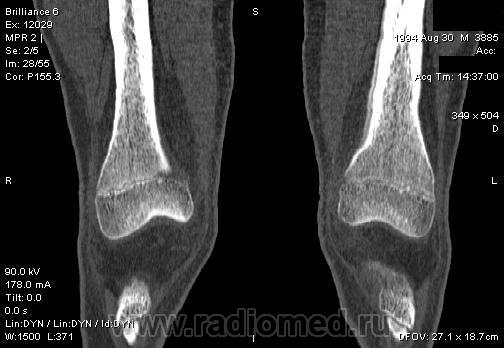

Мальчик 15 лет. Несколько месяцев назад начали беспокоить боли в коленных суставах. Травмы не было. Ребёнку был выставлен диагноз: болезнь Шлаттера, назначено лечение. На фоне лечения отмечалось значительное усиление болей, боли локализовались в левом коленном суставе. При дообследовании выявлена следующая рентгенологическая картина. Наши рентгенологи настаивают на срастающемся переломе. Но: 1) перелом без травмы? 2) бедро так не ломается

В голову приходит остеомиелит или опухоль.

Локальный гиперостоз, выраженный болевой синдром, структура губчатого вещества диафиза не изменена наводит только на остеойд-остеому.

Я бы на первое место поставила патологическую перестройку, так называемый, стрессовый перелом. Мальчик чем-нибудь занимается?

Согласна с Ola-la - рентгенологическая картина более всего соответствует стрессорному перелому, хотя для него характерна локализация в б/берцовой кости. Меня однако, смущает и настораживает клиника - это как раз тот случай, когда я бы не дала 100% гарантии, что так не может манифестировать остеосаркома... Поскольку другие методы (МРТ, сцинтиграфия) вряд ли помогут, я бы взяла пациента на короткое ( 2недели - месяц) динамическое наблюдение.

Да, на мой взгляд, состояние после обычного "травматического перелома" (трещина), не думаю, что имел место "патологический перелом", так как костная ткань "патологически изменена" минимально. "Перистальная реакция"локальная тоже есть, на КТ "локальная  зона склероза" - все это свидетельствует именно об этом. Хотя в памяти у меня хорошо отложился Ваш последний случай о локальном утолщении кортикального слоя, когда "яйца в гнезде" еще не было. То, что анамнестически "травмы не было" - ничего не значит. Вы, по всей видимости, тоже часто встречались с такими случаями, когда ребенок не акцентировал внимание на "травме", как таковой, хотя клиника есть, боль есть. Конечно, рентгенограммы - не дай бог - ни скиалогии, ни структуры.

Буквально заключение гистологов передать не могу (мой недочет, нужно было сразу выложить на сайтОй-ой-ой), но приблизительно помню - данных за специфический процесс нет, картина консолидирующегося перелома.

Так что, по всей видимости, это действительно был стресс-перелом. Который крайне редко встречается. Хоть статейку в журнал пишиУлыбаюсь.